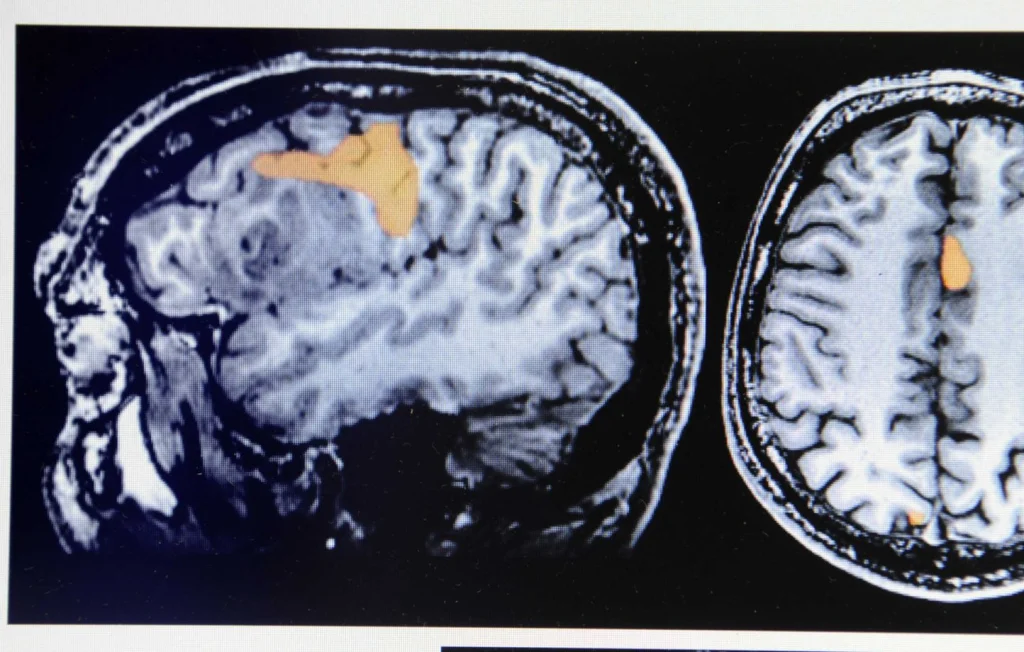

Le tribunal de Florence a condamné un hôpital à indemniser la famille d’un adolescent aujourd’hui âgé de 16 ans, estimant qu’une erreur médicale avait gravement compromis son état de santé. Quand il avait quatre ans, l’enfant a subi deux interventions en 2012 et 2013 visant à retirer ce que les médecins avaient alors diagnostiqué comme une tumeur cérébrale : une ablation partielle du lobe temporal.

Selon les expertises retenues par la justice, l’enfant souffrait en réalité d’une encéphalite herpétique et non d’un cancer. Le traitement adapté à cette inflammation est médicamenteux et non chirurgical, ce qui a conduit les juges à qualifier les opérations d’inutiles et à reconnaître une faute médicale ayant aggravé l’état du patient.